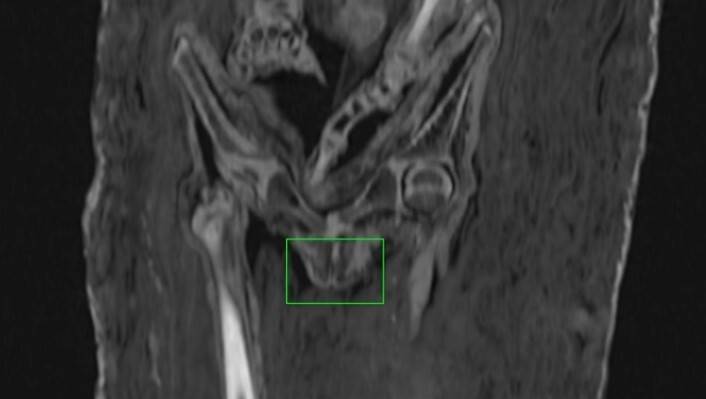

Analizowany portret przedstawia dziecko o owalnej twarzy, pełnych policzkach, dużych oczach i krótkich, ciemnych włosach. Ma ono na sobie purpurową tunikę z ciemnymi pasami i biżuterię: małe złote kolczyki oraz naszyjnik. Już wcześniej badacze różnili się w interpretacji tego wizerunku. Jedni widzieli chłopca, inni dziewczynkę, jeszcze inni wstrzymywali się od jednoznacznej oceny. Sam obraz nie dawał pewnej odpowiedzi. Dlatego kluczową rolę odegrały metody nieinwazyjne przede wszystkim tomografia komputerowa (TK). Dane TK zapisano w formacie DICOM. Uzyskano wyjściowe obrazy w płaszczyźnie poprzecznej a z wykorzystaniem programu OsiriX rekonstrukcje wielopłaszczyznowe oraz modele 3D. Dzięki temu można było zajrzeć do wnętrza mumii bez naruszania bandaży.

Wyniki badań pozwoliły przede wszystkim potwierdzić obecność ciała wewnątrz mumii. Następnie przystąpiono do ustalania płci. Tomografia komputerowa nie wykazała obecności zmumifikowanego prącia. W obrębie miednicy dostrzeżono natomiast tkanki, które mogą odpowiadać żeńskim narządom płciowym, a dodatkowo wydłużoną strukturę interpretowaną ostrożnie jako możliwą macicę. Pomocniczo uwzględniono też kształt żuchwy, który również wskazywał na płeć żeńską. Wniosek autorów był więc jasny: pod bandażami spoczywała dziewczynka.

Równie istotne było ustalenie wieku. Analiza uzębienia wykazała obecność wyrżniętych zębów mlecznych i zawiązków zębów stałych, co sugerowało wiek około 3,5 roku. Pomiary kości długich dawały miejscami niższe wartości, ale inne cechy rozwoju szkieletu, między innymi stadium rozwoju niektórych elementów kończyn dolnych, pozwoliły zawęzić ocenę do podobnego przedziału. Na zdjęciach zauważono również linie Harrisa, czyli poprzeczne ślady zahamowania wzrostu widoczne w obrębie kości długich. Mogą one wskazywać na epizody stresu fizjologicznego, związane na przykład z chorobą albo niedoborami pokarmowymi. Autorzy potraktowali ten trop ostrożnie, ale podkreślili, że mógł on wpływać na różnice między wiekiem ocenianym na podstawie zębów a wiekiem szkieletowym.

Najciekawsze okazało się jednak porównanie tych danych z samym portretem. Wizerunek sugeruje bowiem starsze dziecko, prawdopodobnie w wieku około 6 do 10 lat. Nie daje też pewnej podstawy do określenia płci. Zespół wykonał dodatkowo rekonstrukcję twarzy na podstawie tomografii komputerowej. Powstała najpierw wersja w skali szarości, a następnie wariant barwny, opracowany z wykorzystaniem kolorystyki portretu. Porównanie rekonstrukcji z obrazem wykazało pewne podobieństwa, ale także istotne różnice, zwłaszcza w proporcjach twarzy. Portret przedstawia dziecko jako smuklejsze i starsze, niż wskazują to dane anatomiczne i rekonstrukcja na podstawie badania TK.